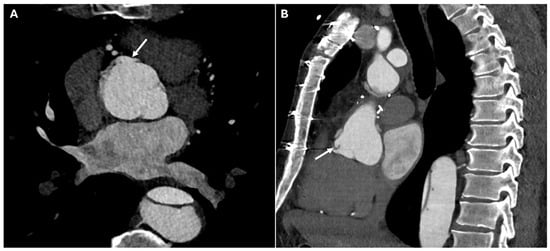

| Pseudoaneurysm | Suture failure, infection, chronic mechanical stress | Contrast-filled sac adjacent to graft, narrow neck | High rupture risk |

| Graft Dehiscence and Leaks | Poor anastomotic integrity, infection, mechanical stress | Contrast extravasation at anastomotic sites, widened mediastinum, disrupted graft margins | Massive hemorrhage |

| Paravalvular Leak | Suture failure, prosthesis malalignment | Contrast extravasation around prosthetic valve annulus | High rupture risk |